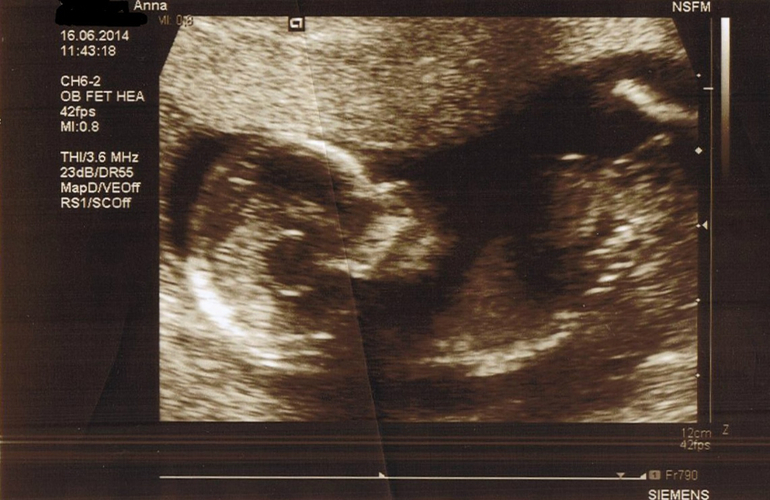

УЗИ в 12+6 нед / Дуо-тест

УЗИ, КТГ, доплерБыли в клинике Св. Олафа, что в Тронхейме, через пару дней после планового обследования. сайт клиники Делали дуо-тест на синдромы Дауна и Эдвардса, который мне полагается пройти по возрасту. Хотя и говорят, что делают его исключительно с 38 лет, но на тот момент мне было только 37 /в августе - 38/. Сделали УЗИ и сдала кровь. Через день позвонили из клиники и сказали, что отклонений нет и мне уже выслали письмо с результатами по почте.